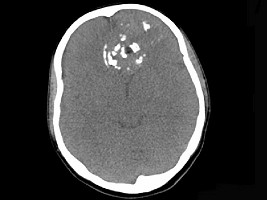

男性,28岁,因鼻塞、头痛1年余,鼻窦CT扫描如图所示,请选择正确的描述与结论 ( ) EBH-00091.jpg EBH-00092.jpg EBH-00093.jpg EBH-00094.jpg

• A.肿块内密度不均,有较多致密钙化影

• B.窦壁及颅底骨质破坏

• C.双侧上颌窦、筛窦、鼻腔及蝶窦内见软组织肿块影

• D.考虑为鼻窦软骨瘤

• E.考虑鼻窦骨瘤